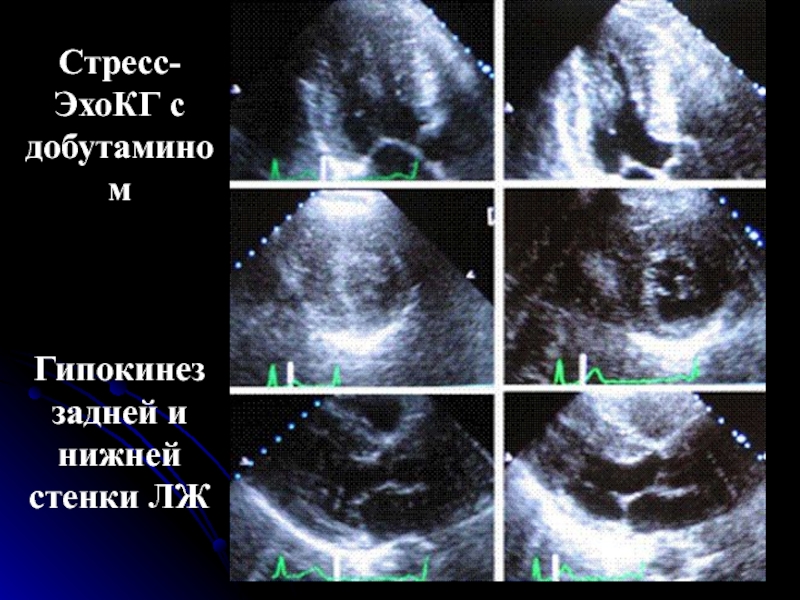

Слайд 31Стресс-ЭхоКГ с добутамином

Гипокинез задней и нижней стенки ЛЖ

Стресс-ЭхоКГ с добутамином Гипокинез задней и нижней стенки ЛЖ